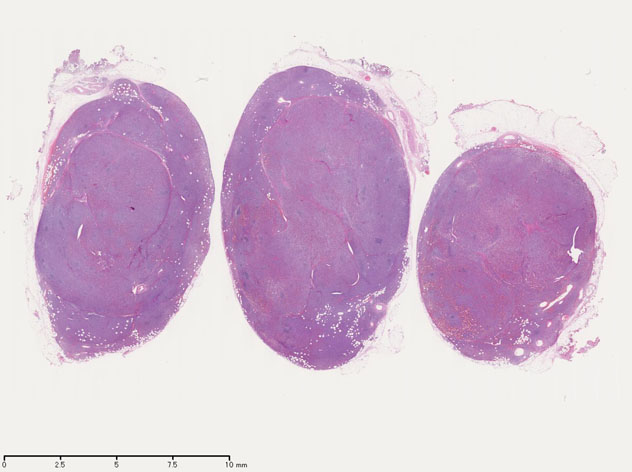

リンパ節病理組織所見

罹患リンパ節の基本構造は消失し腫瘍細胞のびまん性増殖で置換されている。非腫瘍性の小リンパ球(CD3+, CD4/8+)が濾胞様に散在して残る(Fig.01)。不整型または類円形の明るい核をもつmedium-sizeのリンパ球様細胞が密に増殖している。細胞質は乏しい(Fig.02)。CD68陽性macrophageが多く混在する部分が認められた(Fig.03)。